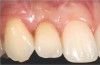

Case 3: Congenitally missing lateral incisors at the sites of teeth Nos. 7 and 10. Both sites were treated simultaneously. (Treatment at the site of tooth No. 10 is illustrated.)

Figure 19

Fig 24. Case 3 (continued): Resin bonded bridge in position (Nos. 9 through 11).

Figure 24

Fig 25. The final crown in place 6 months after implant insertion.

Figure 25